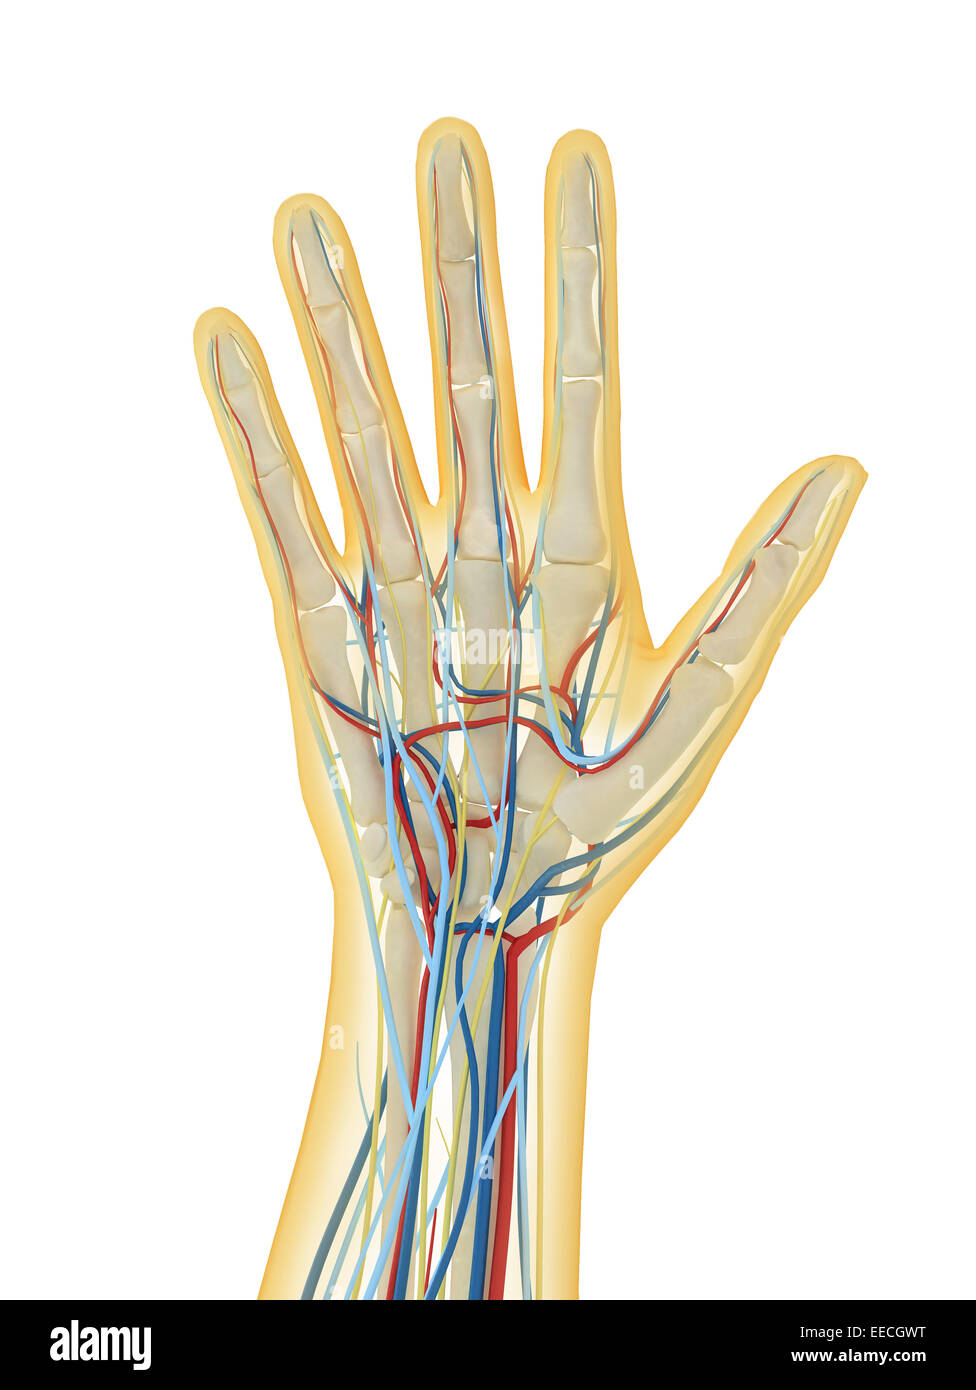

Human hand with nervous system, lymphatic system and circulatory system. Stock Photohttps://www.alamy.com/image-license-details/?v=1https://www.alamy.com/stock-photo-human-hand-with-nervous-system-lymphatic-system-and-circulatory-system-77723348.html

Human hand with nervous system, lymphatic system and circulatory system. Stock Photohttps://www.alamy.com/image-license-details/?v=1https://www.alamy.com/stock-photo-human-hand-with-nervous-system-lymphatic-system-and-circulatory-system-77723348.htmlRFEECGWT–Human hand with nervous system, lymphatic system and circulatory system.